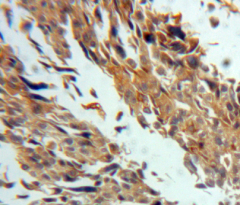

IHC (Immunohiostchemistry)

(Dilution: WB: (1/500 - 1/1000), IH (1/100 - 1/200)Immunohistochemical analysis of RAB6A staining in human breast cancer formalin fixed paraffin embedded tissue section. The section was pre-treated using heat mediated antigen retrieval with sodium citrate buffer (pH 6.0). The section was then incubated with the antibody at room temperature and detected using an HRP conjugated compact polymer system. DAB was used as the chromogen. The section was then counterstained with haematoxylin and mounted with DPX.)